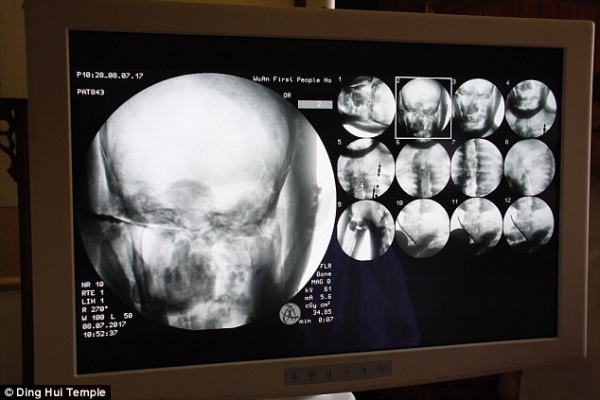

但是經過千年大家才知道這尊佛像裏頭的卻是….根據了解有研究學者透過X光還有XT掃描檢驗,發現驚人的秘密!這是貨真價實的木乃伊,但沒想到最難保存的大腦竟然都還留著!?

當地學者受訪表示:「我們在掃描後發現,他的骨頭跟一般人的一樣完整。」

「上額、上面的牙齒、肋骨、脊椎骨、連關節全部都還在。真的是很驚奇的景象」